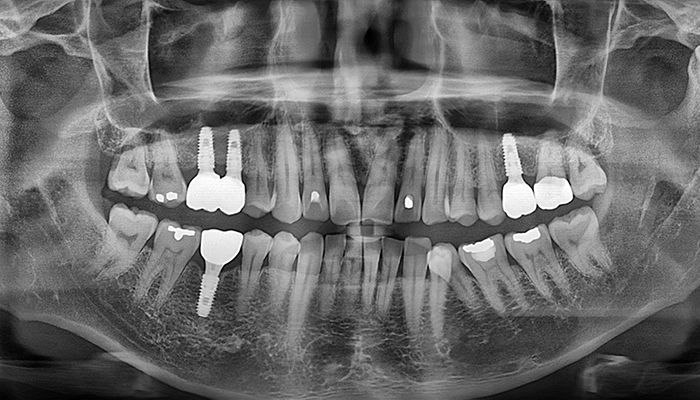

임플란트 수술시, 상악동과 잇몸뼈 사이에 뼈가 남아 있지 않았을 때 상악동막을 들어올리고 빈 공간에 뼈를 이식하여 임플란트 식립을 위한 공간을 확보하는 수술을 상악동 거상술이라 합니다.

밀도가 높고 두꺼운 턱뼈가 구성된 아래턱과는 달리 위턱은 얇은 뼈 위에 코와 광대 사이 빈 공간에 식립해야 하는 고난도 수술로 임플란트 수술 경험이 많은 의료진에게 받는 것이 중요합니다.

치아를 빼고 오래 방치하거나 치아를 잡고 있는 치조골이 많이 녹은상태에서 치아를 빼면 위쪽 턱뼈가 부족할 수 있습니다.